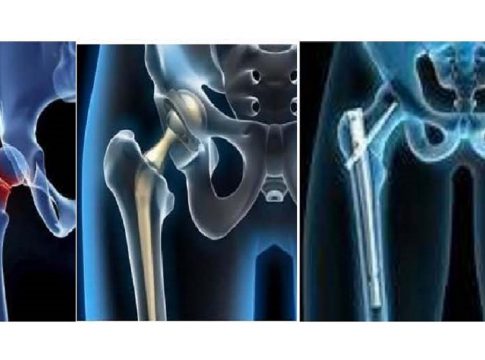

El tratamiento de las fracturas de cadera es quirúrgico (salvo alguna contraindicación importante), y el tipo de cirugía dependerá de dónde se localice la fractura.

«Están las fracturas que ocurren dentro de la cápsula articular de la cadera (intracapsulares, fracturas del cuello de fémur, subcapitales, basicervicales), cuyo tratamiento quirúrgico es una prótesis total o parcial de cadera y en algunos casos, si la fractura no tiene desplazamiento y hay buena calidad ósea se realiza una osteosíntesis, es decir, un sistema de fijación con tornillos canulados. Y las fracturas que se localizan por debajo de la cápsula articular (pertrocantéreas y subtrocantéreas), y su tratamiento es fijar la fractura conservando su cabeza del fémur (clavos intramedulares, tornillo-placa, etc.)»